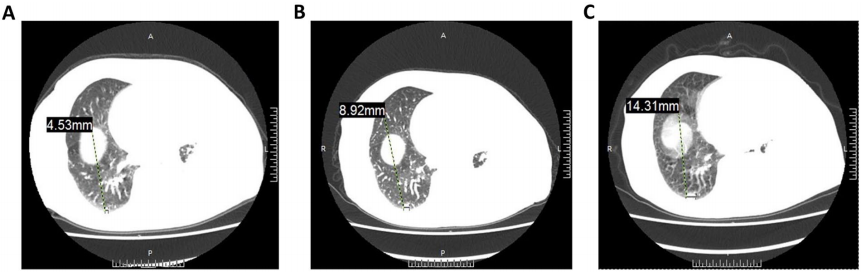

出现严重症状后,对患者血清细胞因子水平的分析表明,干扰素-γ和肿瘤坏死因子α(TNF-α)的表达在第八次治疗时达到峰值(图1)。CT图像显示细胞疗法对治疗肿瘤有一定疗效。具体而言,左肺包裹的胸内液体从46.22 mm减少到33.59 mm(图2A,C),而前气管后腔静脉间质区的淋巴结从11.3 mm减少到8.55 mm(图2B,D)。CT图像显示右肺结节明显大于基线结节(图3)。尽管患者的病情逐渐稳定,但经过一系列对症治疗后,考虑到严重副作用的可能性,她选择退出了这项临床试验。

图2. CCCR-NK92细胞治疗前后肺窗的CT图像。(A)CCCR-NK92细胞治疗前的CT图像。(B)CCCR-NK92细胞治疗一个周期后的CT图像。(C)CCCR-NK92细胞治疗两个周期后的CT图像